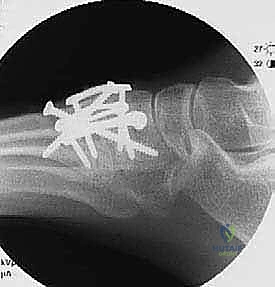

4. Definitive Stabilization: Lag Screws and Compression Staples

First TMT Joint Definitive Stabilization:

- "We'll start with the first TMT joint. Take a 3.5-mm drill sleeve and place it over the more dorsal 0.062 K-wire (the one from the medial cuneiform to the first metatarsal). Use cautery to mark the angulation of this wire on the bone. This helps us maintain the trajectory."

- "Carefully back out the 0.062 K-wire, ensuring the drill sleeve remains fixed in position. Now, using the 3.5-mm drill bit, drill through the near cortex of the medial cuneiform. Then, switch to a 2.5-mm drill bit to create the pilot hole in the far cortex of the first metatarsal. This differential drilling creates a lag effect."

- "Measure your screw length. Countersink the screw head to prevent prominence and soft tissue irritation. Now, insert a 3.5-mm cortical screw in a lag manner. Feel that compression as it bites into the far cortex. That's what we want."

- "Repeat these steps for the second screw, which goes from the first metatarsal to the medial cuneiform. Place a 3.5-mm drill sleeve over the K-wire, mark the trajectory, remove the K-wire, drill with 3.5mm through the near cortex (first metatarsal) and 2.5mm through the far cortex (medial cuneiform), measure, countersink, and insert the 3.5-mm cortical lag screw."

- "Confirm placement and compression with fluoroscopy."